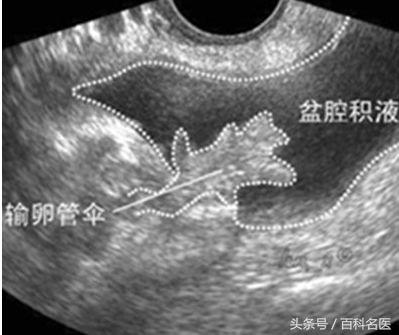

盆腔积液是一种表现而不是一种疾病,确切地说是影像学对盆腔内液体的一种描述。可以分为生理性和病理性两种。生理性的盆腔积液,常常见于部分正常女性在月经期或排卵期,这时会有少量的盆腔积液。便秘的患者,由于肠道蠕动不正常,也引起少量肠液渗出导致盆腔积液,因为盆腔在腹腔中位置是最低的,腹腔中的任何液体渗出,都可能造成盆腔积液。

病理性盆腔积液可发生在盆腔炎、附件炎或子宫内膜异位症之后,为盆腔炎的主要影像学特征。可能由于经期不注意卫生、邻近器官炎症蔓延、产后及妇科手术后感染造成,或者是卵巢及输卵管肿瘤、肝肾疾病均可引起盆腔积液同时伴有腹水,甚至胸水。此外,结核性盆腔炎时,也可产生大量渗出液聚积在盆腔。